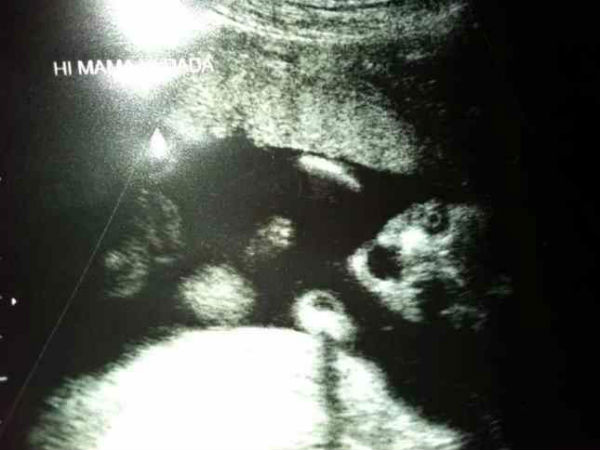

ಚಿತ್ರ #3 ಅಸಾಧ್ಯ ಗಾತ್ರದ ಮಗು

ತನಗೆ ಇಲ್ಲಿ ಸ್ಥಳಾವಕಾಶ ಸಾಕಾಗುತ್ತಿಲ್ಲ, ನನಗೆ ತಕ್ಷಣ ಹೊರಬರಬೇಕು ಎಂದು ಹೇಳುತ್ತಿರುವಂತಿದೆ ಈ ಚಿತ್ರ. ಈ ಮಗುವಿನ ಗಾತ್ರ ಸಾಮಾನ್ಯಕ್ಕಿಂತಲೂ ತುಂಬಾ ಹೆಚ್ಚಾಗಿದ್ದು ಚಿತ್ರದ ಹೆಚ್ಚಿನ ಭಾಗವನ್ನು ಆವರಿಸಿಕೊಂಡಿರುವ ಕಾರಣ ಈ ಬಗೆಯ ಯೋಚನೆ ನಿಮ್ಮಲ್ಲೂ ಮೂಡಿರಬಹುದು.